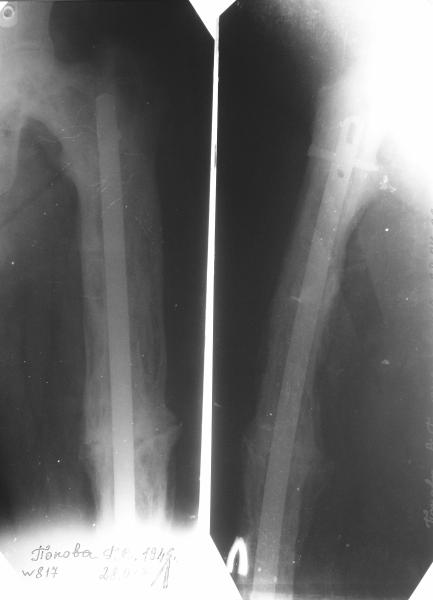

Еще один пример. Пациентка с юга России, прислала рентгенограммы через год. На сегодня прошло 2 г. 8 мес. после операции. Несмотря на не очень убедительный процесс сращения, пациентка ходит. Учитывая остеопороз при Педжете, решили, что динамизировать вообще не нужно.